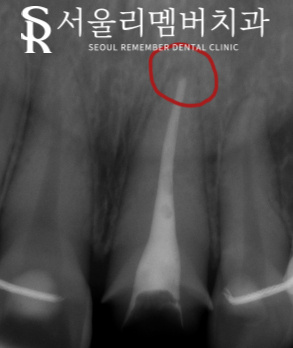

신길동 치과 에서는 방사선 사진으로 보이듯이 근관 안에 대체 약물을 채워 넣었습니다.

이곳은 원뿔형 모양으로 생겼는데요. 뿌리 끝부분까지 꼼꼼하게 채워주는 것이 중요합니다.

꼼꼼히 없애지 않았다면 통증이 계속될 수도 있고

추후에 시간이 흘러 뿌리 끝에 염증이 생길 수 있기 때문에

끝부분까지 제거하고 약물로 채워주는 것이 중요합니다.